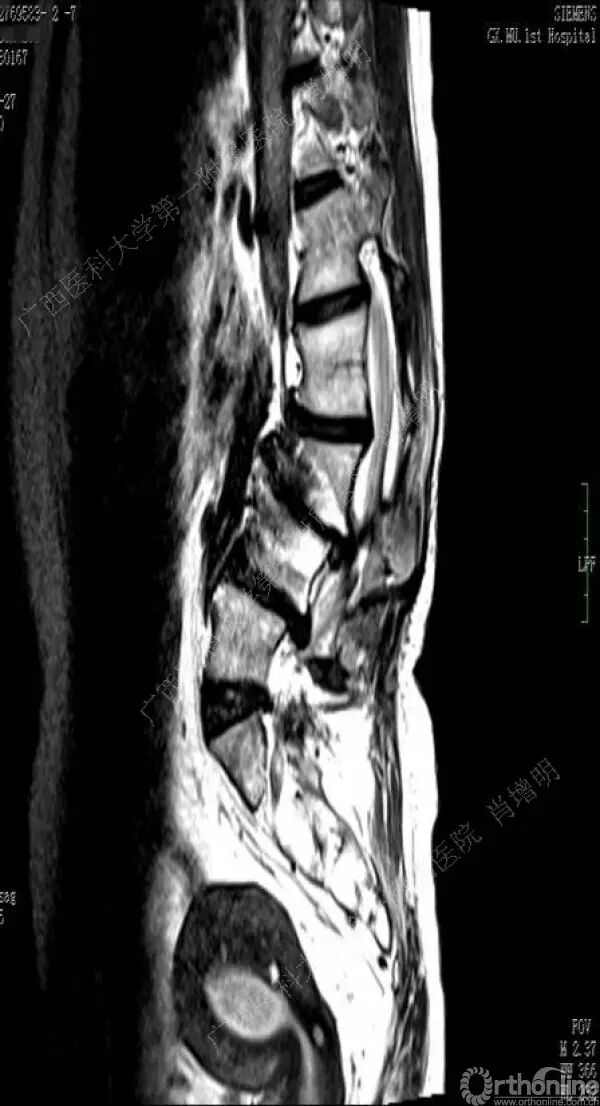

退变性脊柱侧凸是由于椎间盘退变后继发小关节退变,椎管和神经根管容积变化以及脊柱失稳,畸形等病理改变,以疼痛和神经压迫症状为主要表现的常见疾病。

退变性脊柱侧凸多发于50岁以上的中老年群体,是现代常见的老年疾病。多年来,针对该病的临床研究一直没有停步,广西医科大学第一附属医院肖增明教授细致地介绍了该病的诊疗进展。